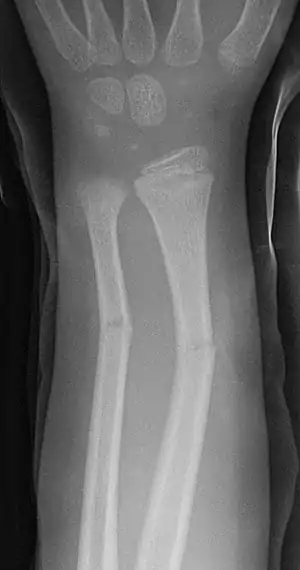

Greenstick fracture

A greenstick fracture is a fracture in a young, soft bone in which the bone bends and breaks. Greenstick fractures occur most often during infancy and childhood when bones are soft. The name is by analogy with green (i.e., fresh) wood which similarly breaks on the outside when bent.

| Greenstick fractures on X-ray. | |